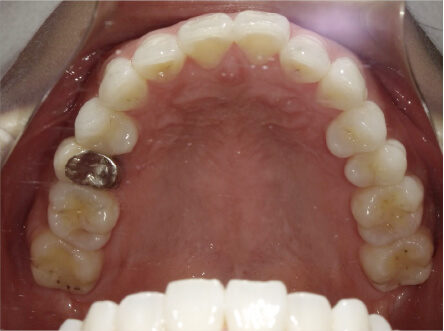

叢生の症例

9歳

/

女性

相談内容

マイオスマイルからの移行

カウンセリング・診断結果

上11捻転、上33スペース不足、インビザで歯列矯正

治療内容・方法

全額アライナー矯正 クリアコレクト

術後の経過・現在の様子

リンガルアーチ使用

治療のリスク

痛み・歯根吸収・歯肉退縮・虫歯・後戻り

費用・治療期間

(マウスピース矯正のみ)440,000円+220,000円 月々27,500円、9ヶ月+myo1年10ヶ

トレーニングなど